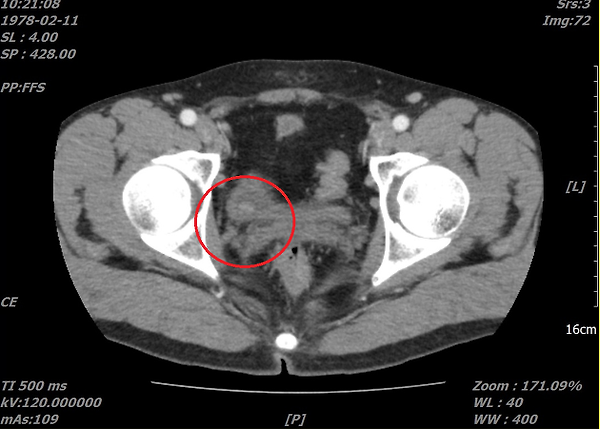

위사진은 암으로 추측되는부분이라도 개인병원 의사가 찾아주신 자료 중 하나입니다.

이게 맞을까요? 첫번째  2011년, 그다음 2015년 세번째도 2011년 그다음 2016년입니다. ....

CT 사진은 음양차이가 굉장히 중요하며 핸드폰으로 찍으신 사진으로는 판단하기가 힘드네요. 마지막 사진방광의 사진상왼쪽에 주변보다 하얗게 보이는 것이 암 소견입니다.

사진상에 보이는 것은 네번째 마지막 사진에만 확실한 종양의심부분이 관찰이 되고 있습니다.

아. 정확히 보이시네요.

첫번째 사진 2011년 4월22일 ENHANCE CT 영상에서도

동그라미 쳐진 부분(화살표) 부분이 조영증강된 것이 확인이 됩니다.

나머지도 보시기 쉽게 동그라미 표시를 해드렸습니다.